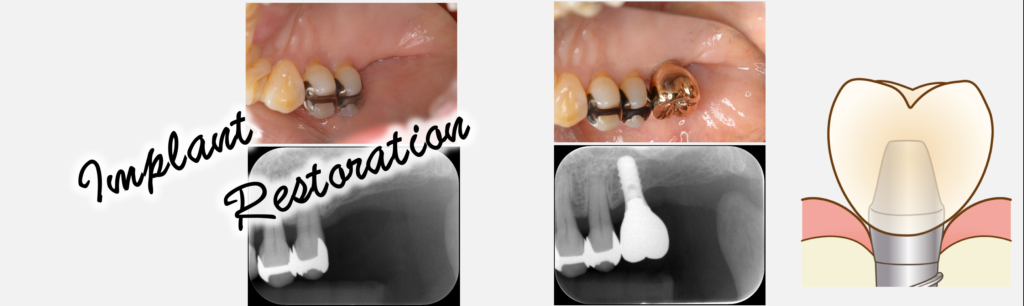

インプラント治療について

トップページ 〉診療案内〉インプラント治療とは? 当院におけるインプラント治療について インプラント無料相談 インプラントとは インプラントとは、体内に埋め込む医療機器や材料の総称をいいます。心臓のペー … 続きを読む インプラント治療について